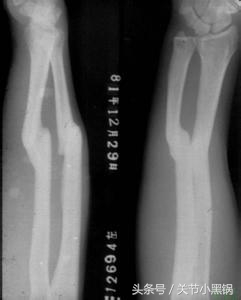

石膏固定

简单理解:石膏固定就是对于一些相对比较小型的骨折或者非负重区域的骨折采用石膏固定或者用于矫形,避免骨折进一步移位的技术或者达到矫形的目的,当然,像上图那样石膏固定了之后也是不能下地行走的!!

石膏固定主要针对的是一些微小的骨折,比如说上肢的骨折等,存在以下缺点:

1、骨折不能绝对固定,可能存在骨折再次移位的可能,甚至因为骨折再次移位损伤周围血管及神经造成严重并发症;

2、石膏固定后,固定的地方会发生肿胀,如果石膏过松可能起不到固定的作用,石膏过紧的话,肢体肿胀明显有可能引起血液循环障碍,小腿及手臂石膏固定引起的最严重的不良反应临床称为骨筋膜室综合征,严重时可能导致截肢;

3、石膏固定过紧或者与皮肤接触部位不平的话可能导致局部压迫缺血,把皮肤压烂造成感染,小孩子或者老年人抵抗力较低的可能感染波及全身,甚至影响生命;

4、石膏固定用于矫形者,比如说小孩子先天性马蹄内翻足的治疗,需要定时更换;

5、石膏固定必须先行手法复位,因为不是直视下复位,因此骨折不能达到解剖复位,有可能存在对线对位的异常,可能存在畸形愈合,影响患者预后;

6、影响生活质量,睡觉的时候也要带着!!!

因此,微小的骨折或者非负重区域的骨折可以考虑石膏固定,但也必须同患者及其家属告知相关替代方案及可能出现的并发症,由患者来选择!